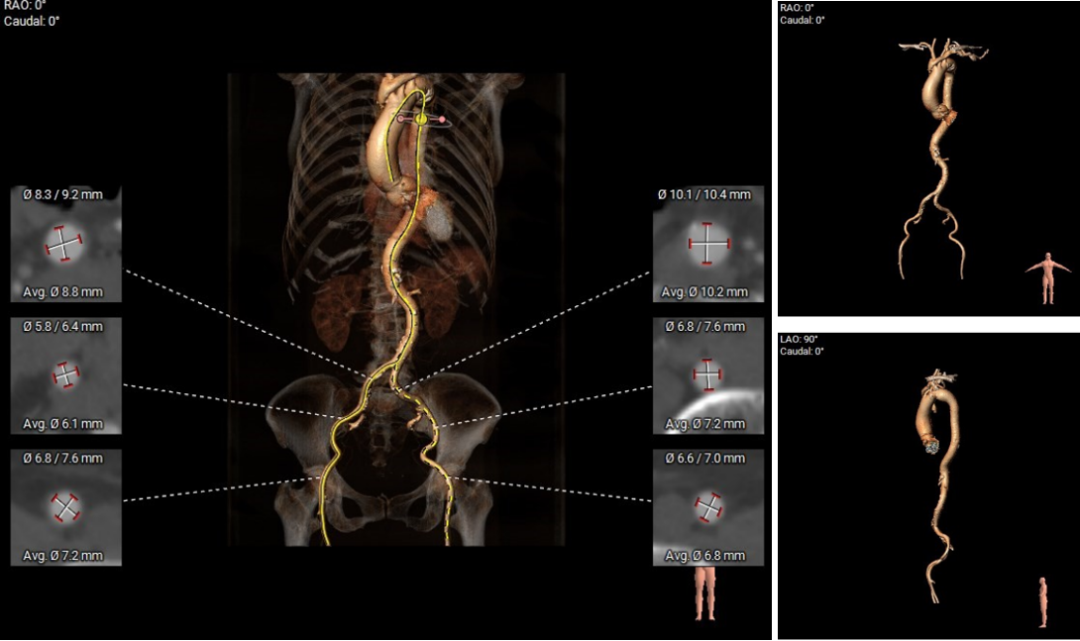

术前评估:

1.主动脉瓣瓣环周长80.9mm,平均周长径25.8mm;

2.Type0型二叶式主动脉瓣,中度钙化,瓣叶增厚,左室流出道呈收口状;

3.左右冠共窦,冠脉开口高度可,左、右冠瓣叶长度<冠脉开口到瓣叶附着缘距离;

4.瓦式窦、窦管交界、升主动脉内径尚可;

5.瓣环水平夹角66°,横位心,主动脉弓宽度、角度可;

6.双侧外周入路行走适宜,未见明显迂曲。

主动脉根部评估:

图片

根部预览

根部评估

瓣上评估

外周血管及主动脉弓解剖